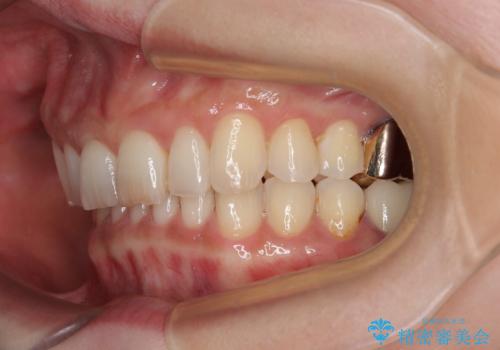

デコボコの歯とむし歯 インビザライン矯正治療とむし歯治療

- 奥歯が咬めないくらいに痛いとのことで来院された患者様です。

痛みの強い歯は、歯髄組織が強い炎症を起こしており、神経を取り除く必要であったため、速やかに根管治療を行いました。

その後、オールセラミッククラウンにて補綴治療を行う予定でしたが、処置した歯以外にも治療が必要と思われる歯があったり、デコボコした歯列も気になるとのことで、患者様希望によりインビザラインにてマウスピース矯正を行うこととしました。

まずは矯正治療前に必要なむし歯処置を行い、その後矯正治療を行ってから、最後にオールセラミッククラウンなどで補綴治療を行うこととしました。

咬合力が非常に強く、全体的に歯が擦り減っている状態であったので、理想的な咬み合わせを達成することは難しく、また咬合力が強い方のマウスピース矯正は、思い通りに動かないことがあるため、ワイヤー矯正の方が望ましいように思えました。